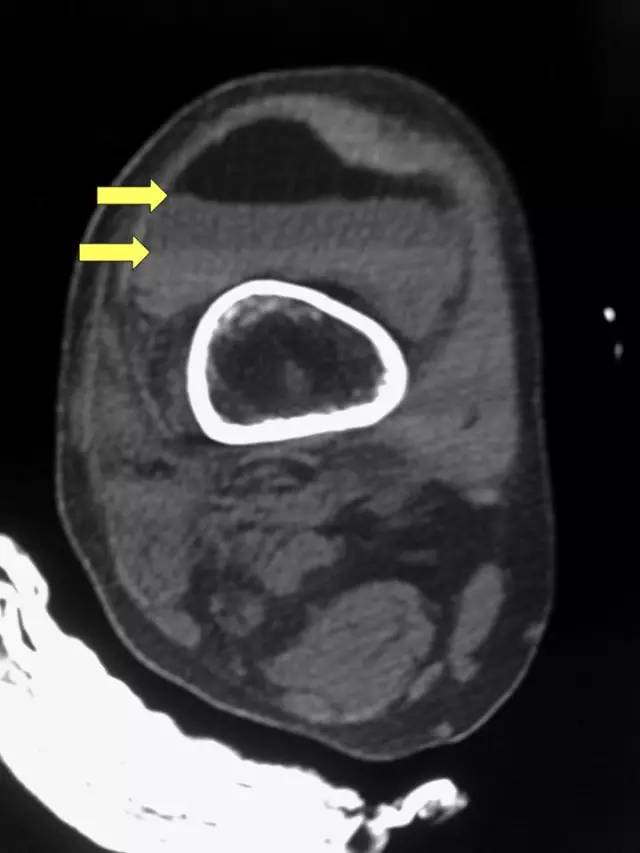

脂—液平面征(FBI;fat/blood/interface)见于关节积脂血症。

发生关节囊内骨折后,从骨髓腔或撕裂的骨膜处溢出的脂肪组织和血液同时进入关节腔内。由于血液密度相对较大,沉于关节液之下,而脂肪密度相对小,漂浮于关节液之上,从而形成分层现象,即影像上所说的脂肪-血液界面征(fat-blood interface sign,FBI sign)。血液中的气体也可以释放出来,在关节囊内形成低密度气泡,此即关节积气脂血病(pneumolipohemarthrosis)。

CT表现:CT可以清楚地显示关节腔内的脂肪和血液及两者形成的液-液平面,有时还可以出现3层,即上层为脂肪,中层为关节液,下层为血液。关节囊内的脂肪CT值约为-130~-100 HU,而关节囊内的血液CT值约为10~30 HU。有时出血和关节腔积液分辨不清,常被笼统地认为关节腔积液。